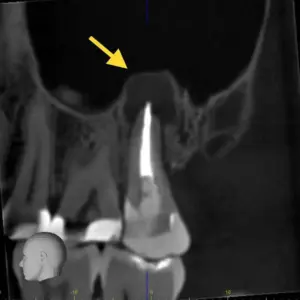

Đẩy lưỡi là một chức năng phổ biến nhất của lưỡi, rối loạn chức năng của lưỡi, có thể được đánh giá trên lâm sàng bằng kiểm tra, phân tích phim, chụp X-quang.

Kiểm tra chức năng phát âm và thần kinh, phim cephalogram có thể giúp đánh giá vị trí kích thước của lưỡi trong mối tương quan của khoang miệng